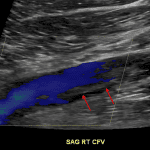

Indication: Bilateral lower extremity swelling and pain

- Intraluminal echogenic material in the right common femoral, femoral, profunda femoral, and greater saphenous veins with incomplete compressibility and thickening of the wall of the common femoral vein

- Flow is present in these veins on color Doppler analysis

Chronic deep venous thrombosis

Partially occlusive thrombus in the right common femoral, femoral, profunda femoral, and greater saphenous veins, favored chronic. Preserved flow in these veins.